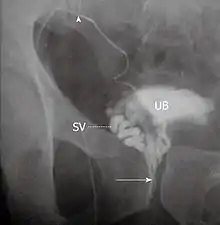

Vasography is an X-ray study of the vas deferens to see if there is blockage, oftentimes in the context of male infertility.[1] An incision is made in the scrotum, contrast is injected in the vas deferens, and X-rays are taken from different angles.[1] Thus, it is an invasive procedure and carries risk of iatrogenic scarring and obstruction of the vas.[2] Vasography has traditionally been considered the gold standard imaging modality for evaluating the seminal tract patency.[3]